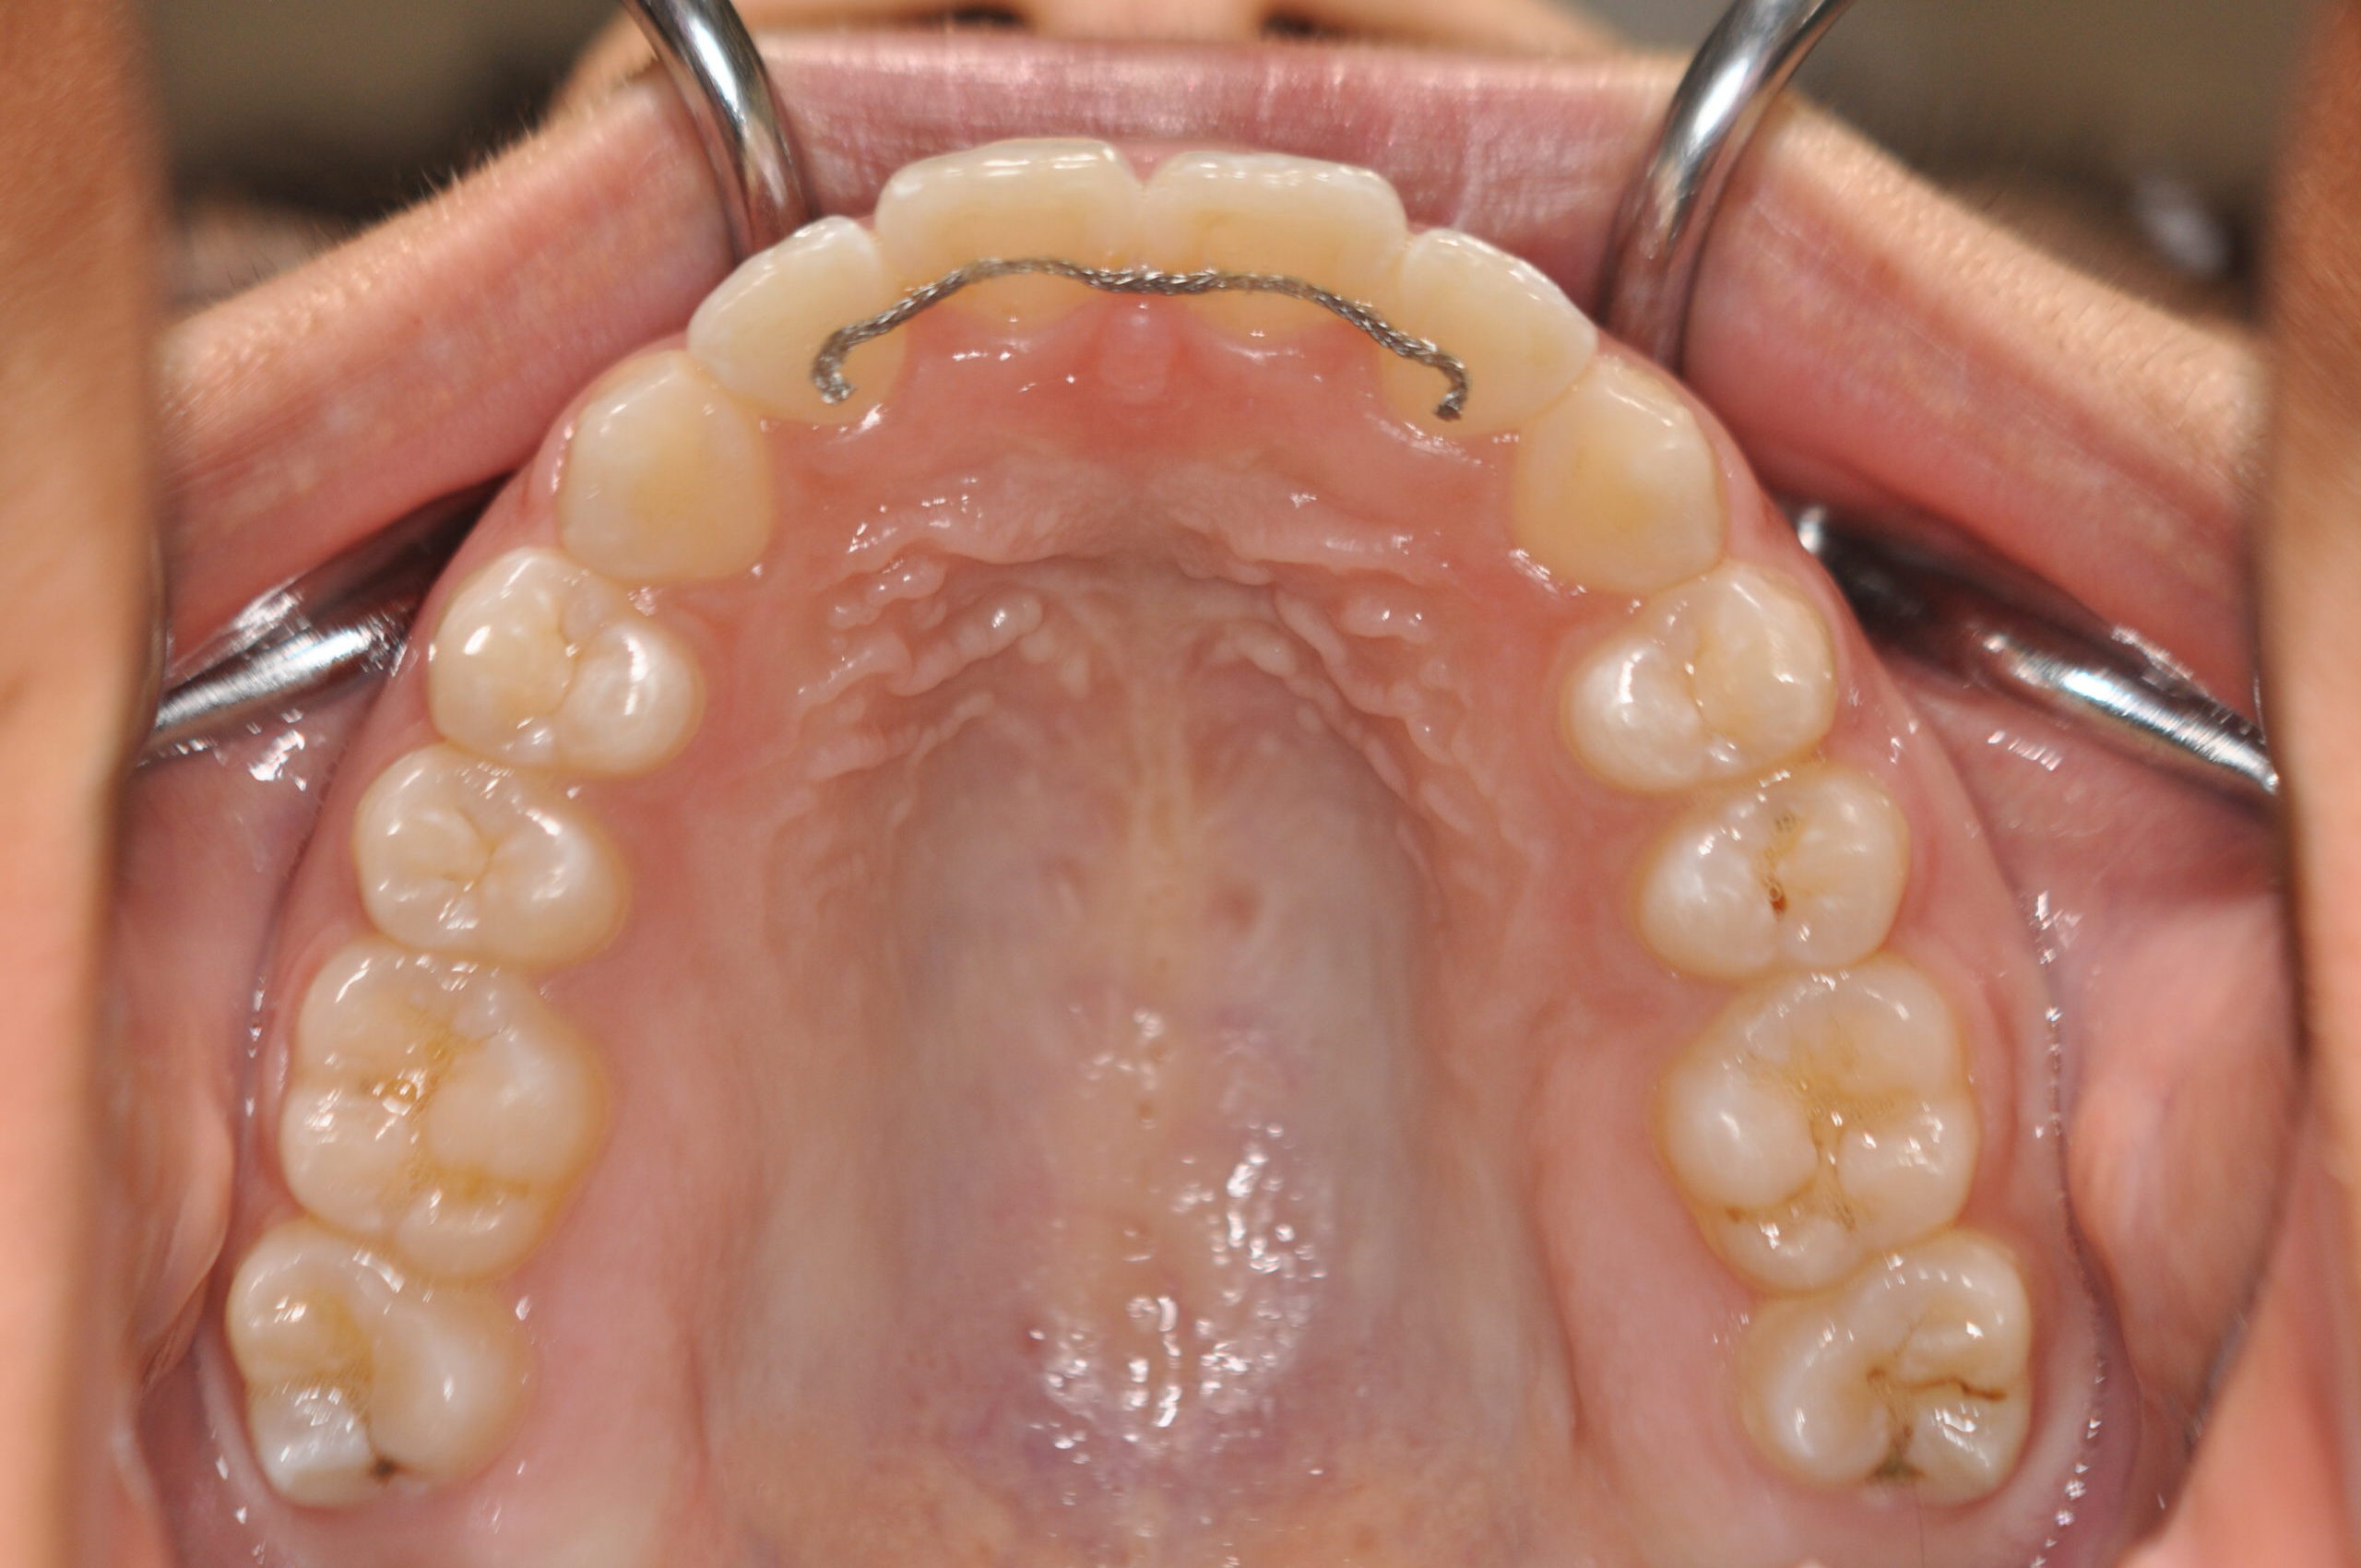

| 治療内容の詳細 | 初診時14歳の女性で、歯のがたつき、かみ合わせを気にされ来院されました。 検査の結果、上下顎前歯部叢生および開咬を伴うアングルⅠ級不正咬合と診断しました。 治療としては、非抜歯の上、セルフライゲーションブラケット装置(デーモンシステム)と マウスピース矯正装置(インビザライン)で配列を行いました。 開咬については、顎間ゴムの協力もあり改善されました。 治療期間は、2年2ヶ月でした。 |